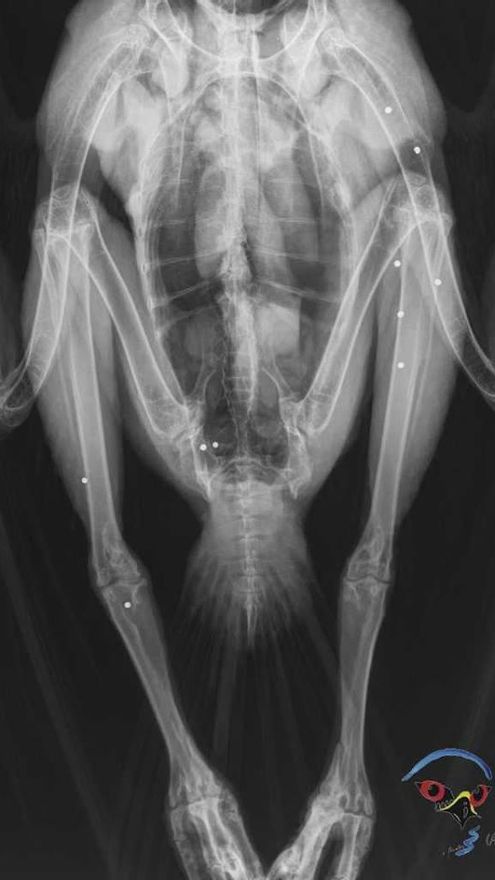

Recogen a una hembra de águila real en el sur de Extremadura con 14 impactos de perdigón

El águila había tenía hasta 14 perdigones de plomo / AMUS Oficial (Acción por el Mundo Salvaje)

El hospital de la asociación Acción por el Mundo Salvaje (AMUS)  en Villafranca de los Barros ha recogido una hembra de águila real, especie protegida, que presentaba 14 impactos de perdigón tras ser disparada en tierras del sur de Extremadura.